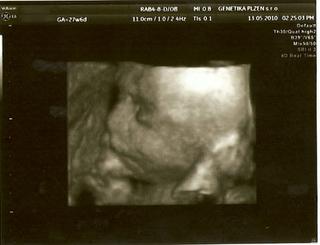

Dneska jsem byla znovu na tom 3D UTZ a miláček náš maličkej (zase tak maličkej není, dle MS 27+6 ale dle UTZ 29+0 a odhad váhy 1300g 😵 ) úžasně spolupracoval, takže teď jdu naskenovat fotečky a za chvíli vám je ukážu 😵

tak naskenováno 😵

Tak ty fotky jsou absolutně boží!!!!

Micha, fotečky Vojtíška jsou naprosto úžasné 🙂 Moc mu to sluší... To byl zážitek, co?